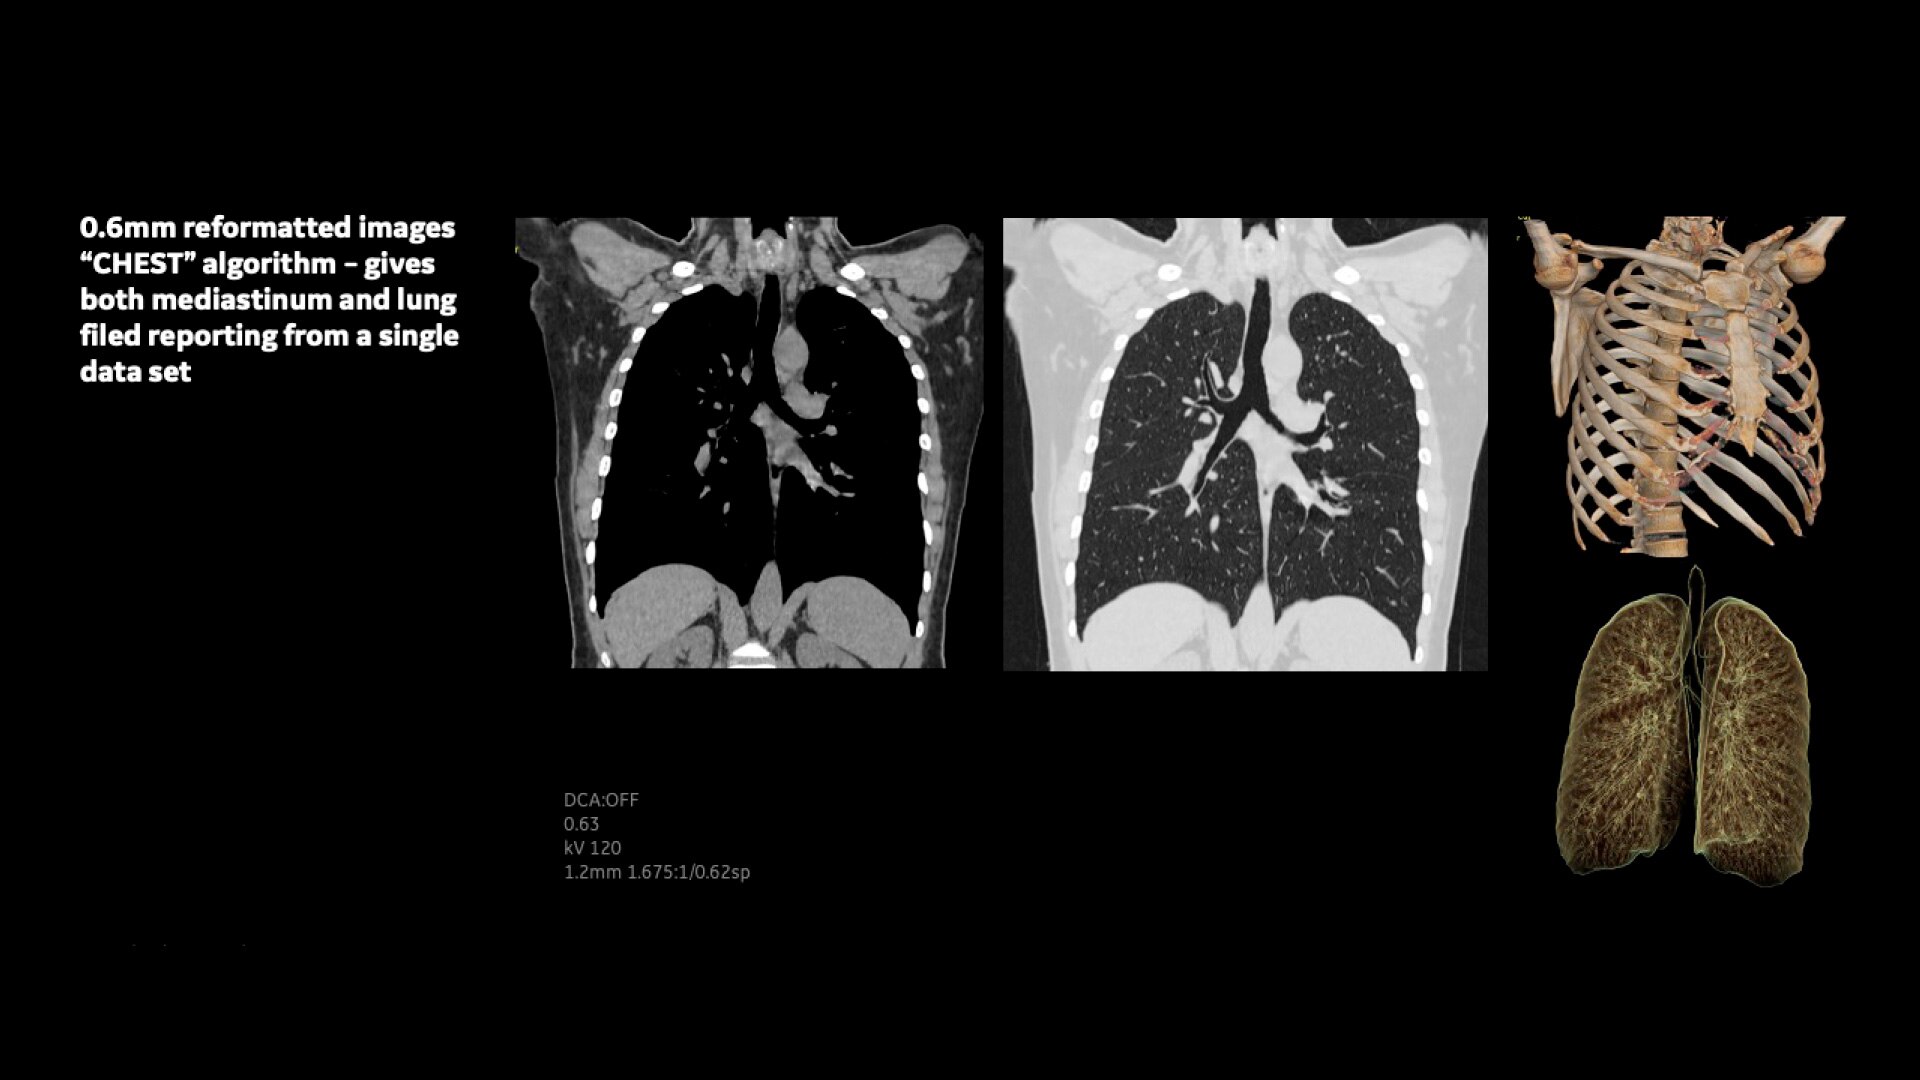

Innovative imaging chain – The Clarity Imaging Chain consists of the Atlas Panel Detector, X-ray Tube, Compact High-voltage Generator, and optional ASiR reconstruction. It delivers high spatial resolution with low noise and less artifact to meet various customer needs in real clinical situations.

Volume Viewer – Provides information about the spatial relationships using volume rendering, multi-planar reformat, and MIP/min-MIP.